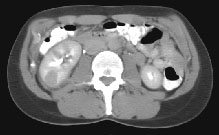

HELICAL CT FINDINGS: The CT was performed on AIC’s multi-slice helical CT (MSCT) scanner. Images with 5 mm collimation were obtained before, immediately following and 5-10 minutes after power injection of IV contrast. The region of the appendix was unremarkable. However, the right kidney and perinephric region were abnormal. Fig. 1 and Fig. 2 illustrate patchy and wedge-shaped low attenuation areas in the right kidney, and Fig. 3 shows stranding/infiltration of perinephric fat around the lower pole consistent with inflammatory changes (arrows).

DIAGNOSIS: The CT images are most compatible with acute pyelonephritis (APN) even without any laboratory results. Shortly after, results of blood work and urinalysis revealed leukocytosis and pyuria substantiating the CT diagnosis.